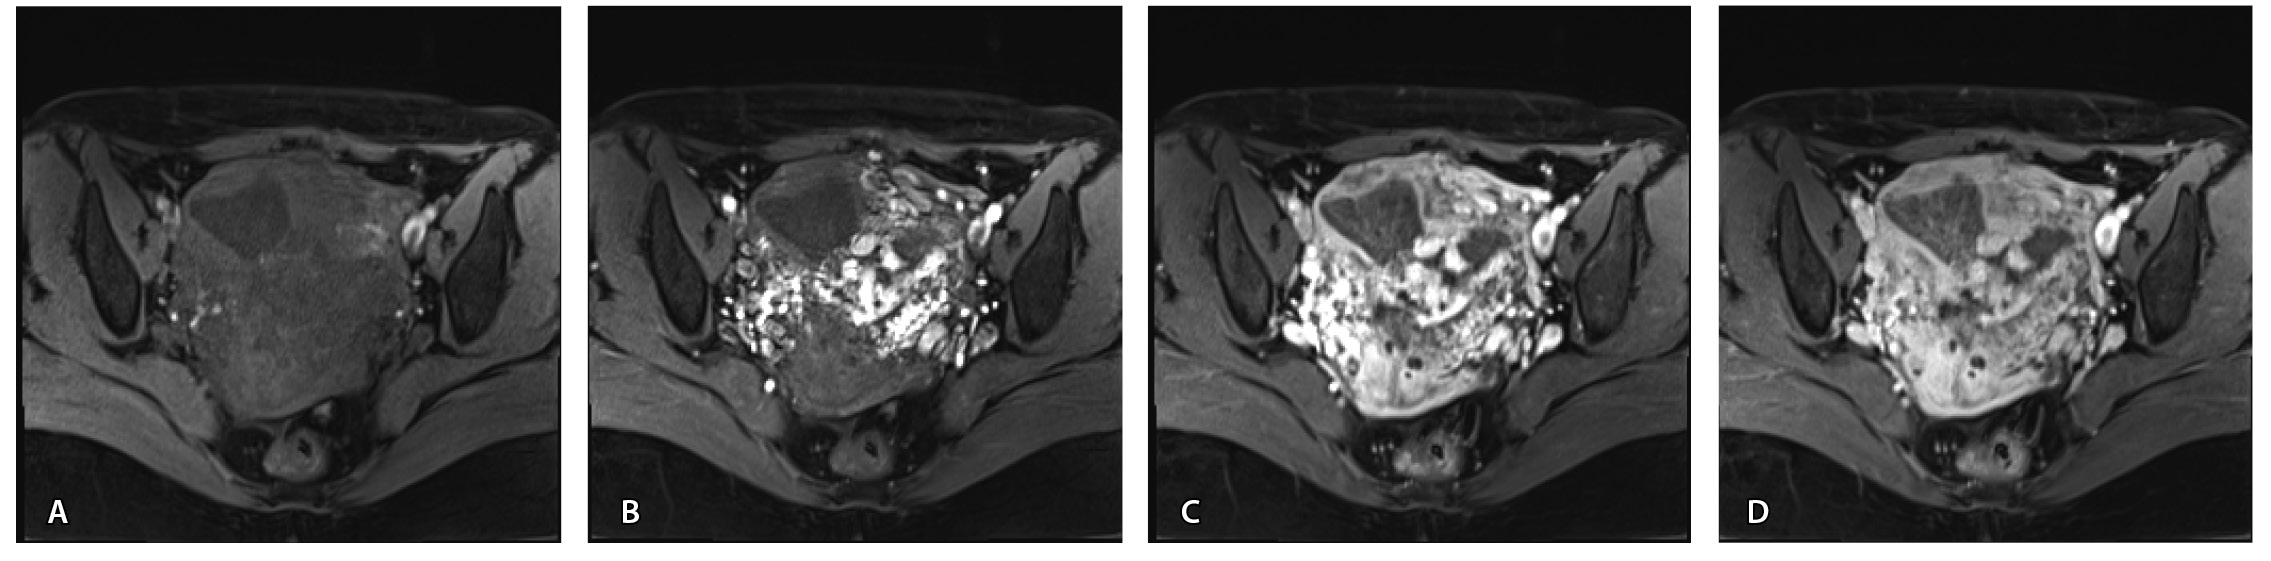

Для детализации сосудистого компонента артериовенозной мальформации, в том числе с целью планирования дальнейшей лечебной тактики, пациентке выполнено КТ-исследование (рис. 3). Обнаружено: тело матки увеличено, определяется образование в полости матки неясного генеза. В стенках матки сосудистая артериальная сеть с ранним сбросом контрастного вещества во внутреннюю подвздошную вену с двух сторон (диаметром 0,7 см справа, 0,8 см – слева), правую яичниковую вену (диаметром до 1,2 см), левую яичниковую вену (диаметром до 0,6 см).

Рис. 3. Компьютерная томограмма органов таза с контрастированием. Тело матки увеличено, в стенках матки сосудистая артериальная сеть (стрелки) с ранним сбросом контрастного вещества во внутреннюю подвздошную вену с двух сторон, правую и левую яичниковые вены (стрелка)